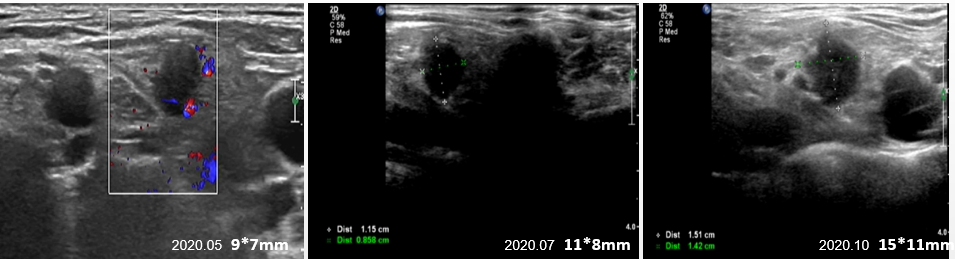

建议干预,患者要求考虑并继续维持方案:曲妥珠单抗300mg Q3W+吡咯替尼320mg QD+卡培他滨1.0g BID+唑来膦酸4mg Q4W。维持至2020.10,右锁骨上LN进行性增大,余未见异常(图4)。

图4. 右侧锁骨上淋巴结回声影像图